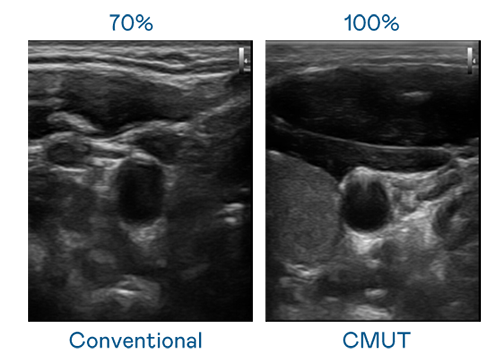

CMUT 技术是一种用电容式微机电元件来产生超音波讯号的技术。与传统 PZT 压电式技术相比,CMUT 频宽增加 30%,更宽频的超音波讯号让影像解析度大幅提升,是实现高影像品质医疗超音波扫描、促进精准医疗发展的关键技术。

大频宽带来超清晰影像

超音波影像的解析度高低,首先取决于探头能发出的讯号频宽。美高梅mgm CMUT 可提供高清晰的超音波讯号,提供高频宽、高灵敏度、影像纹理细节更高的超音波影像,协助医护人员缩短影像判读时间及利用精准的医疗影像进行诊断。